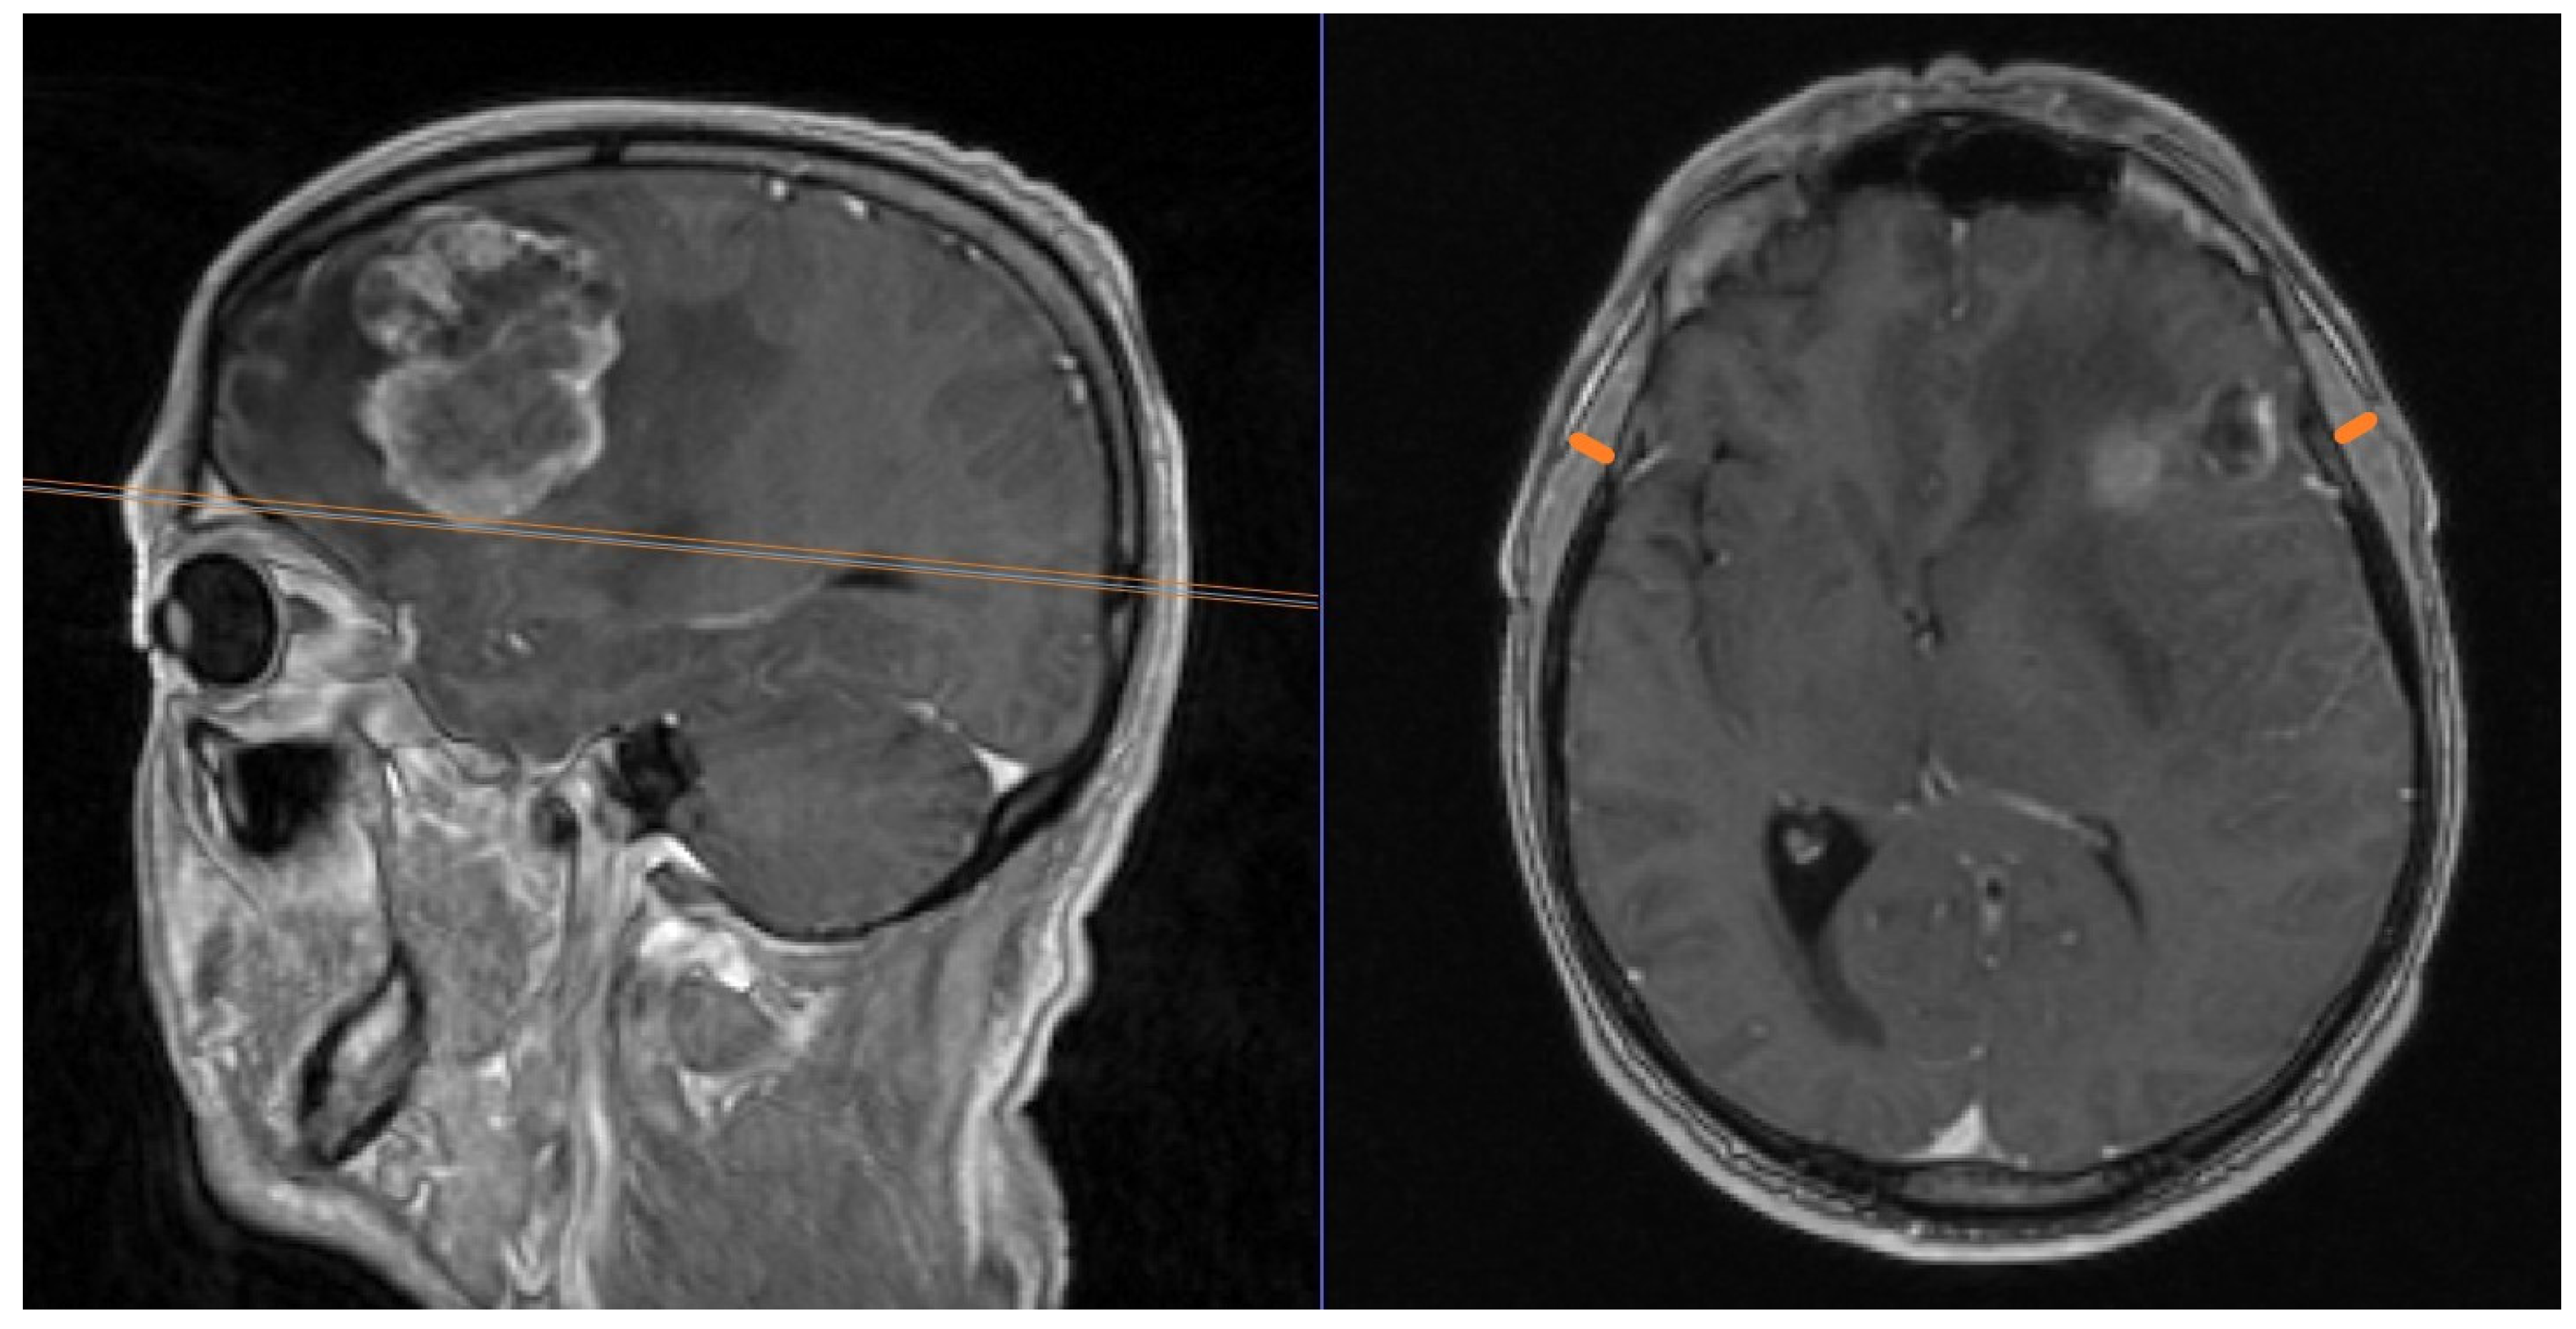

3.2. TMT and Functional Scores